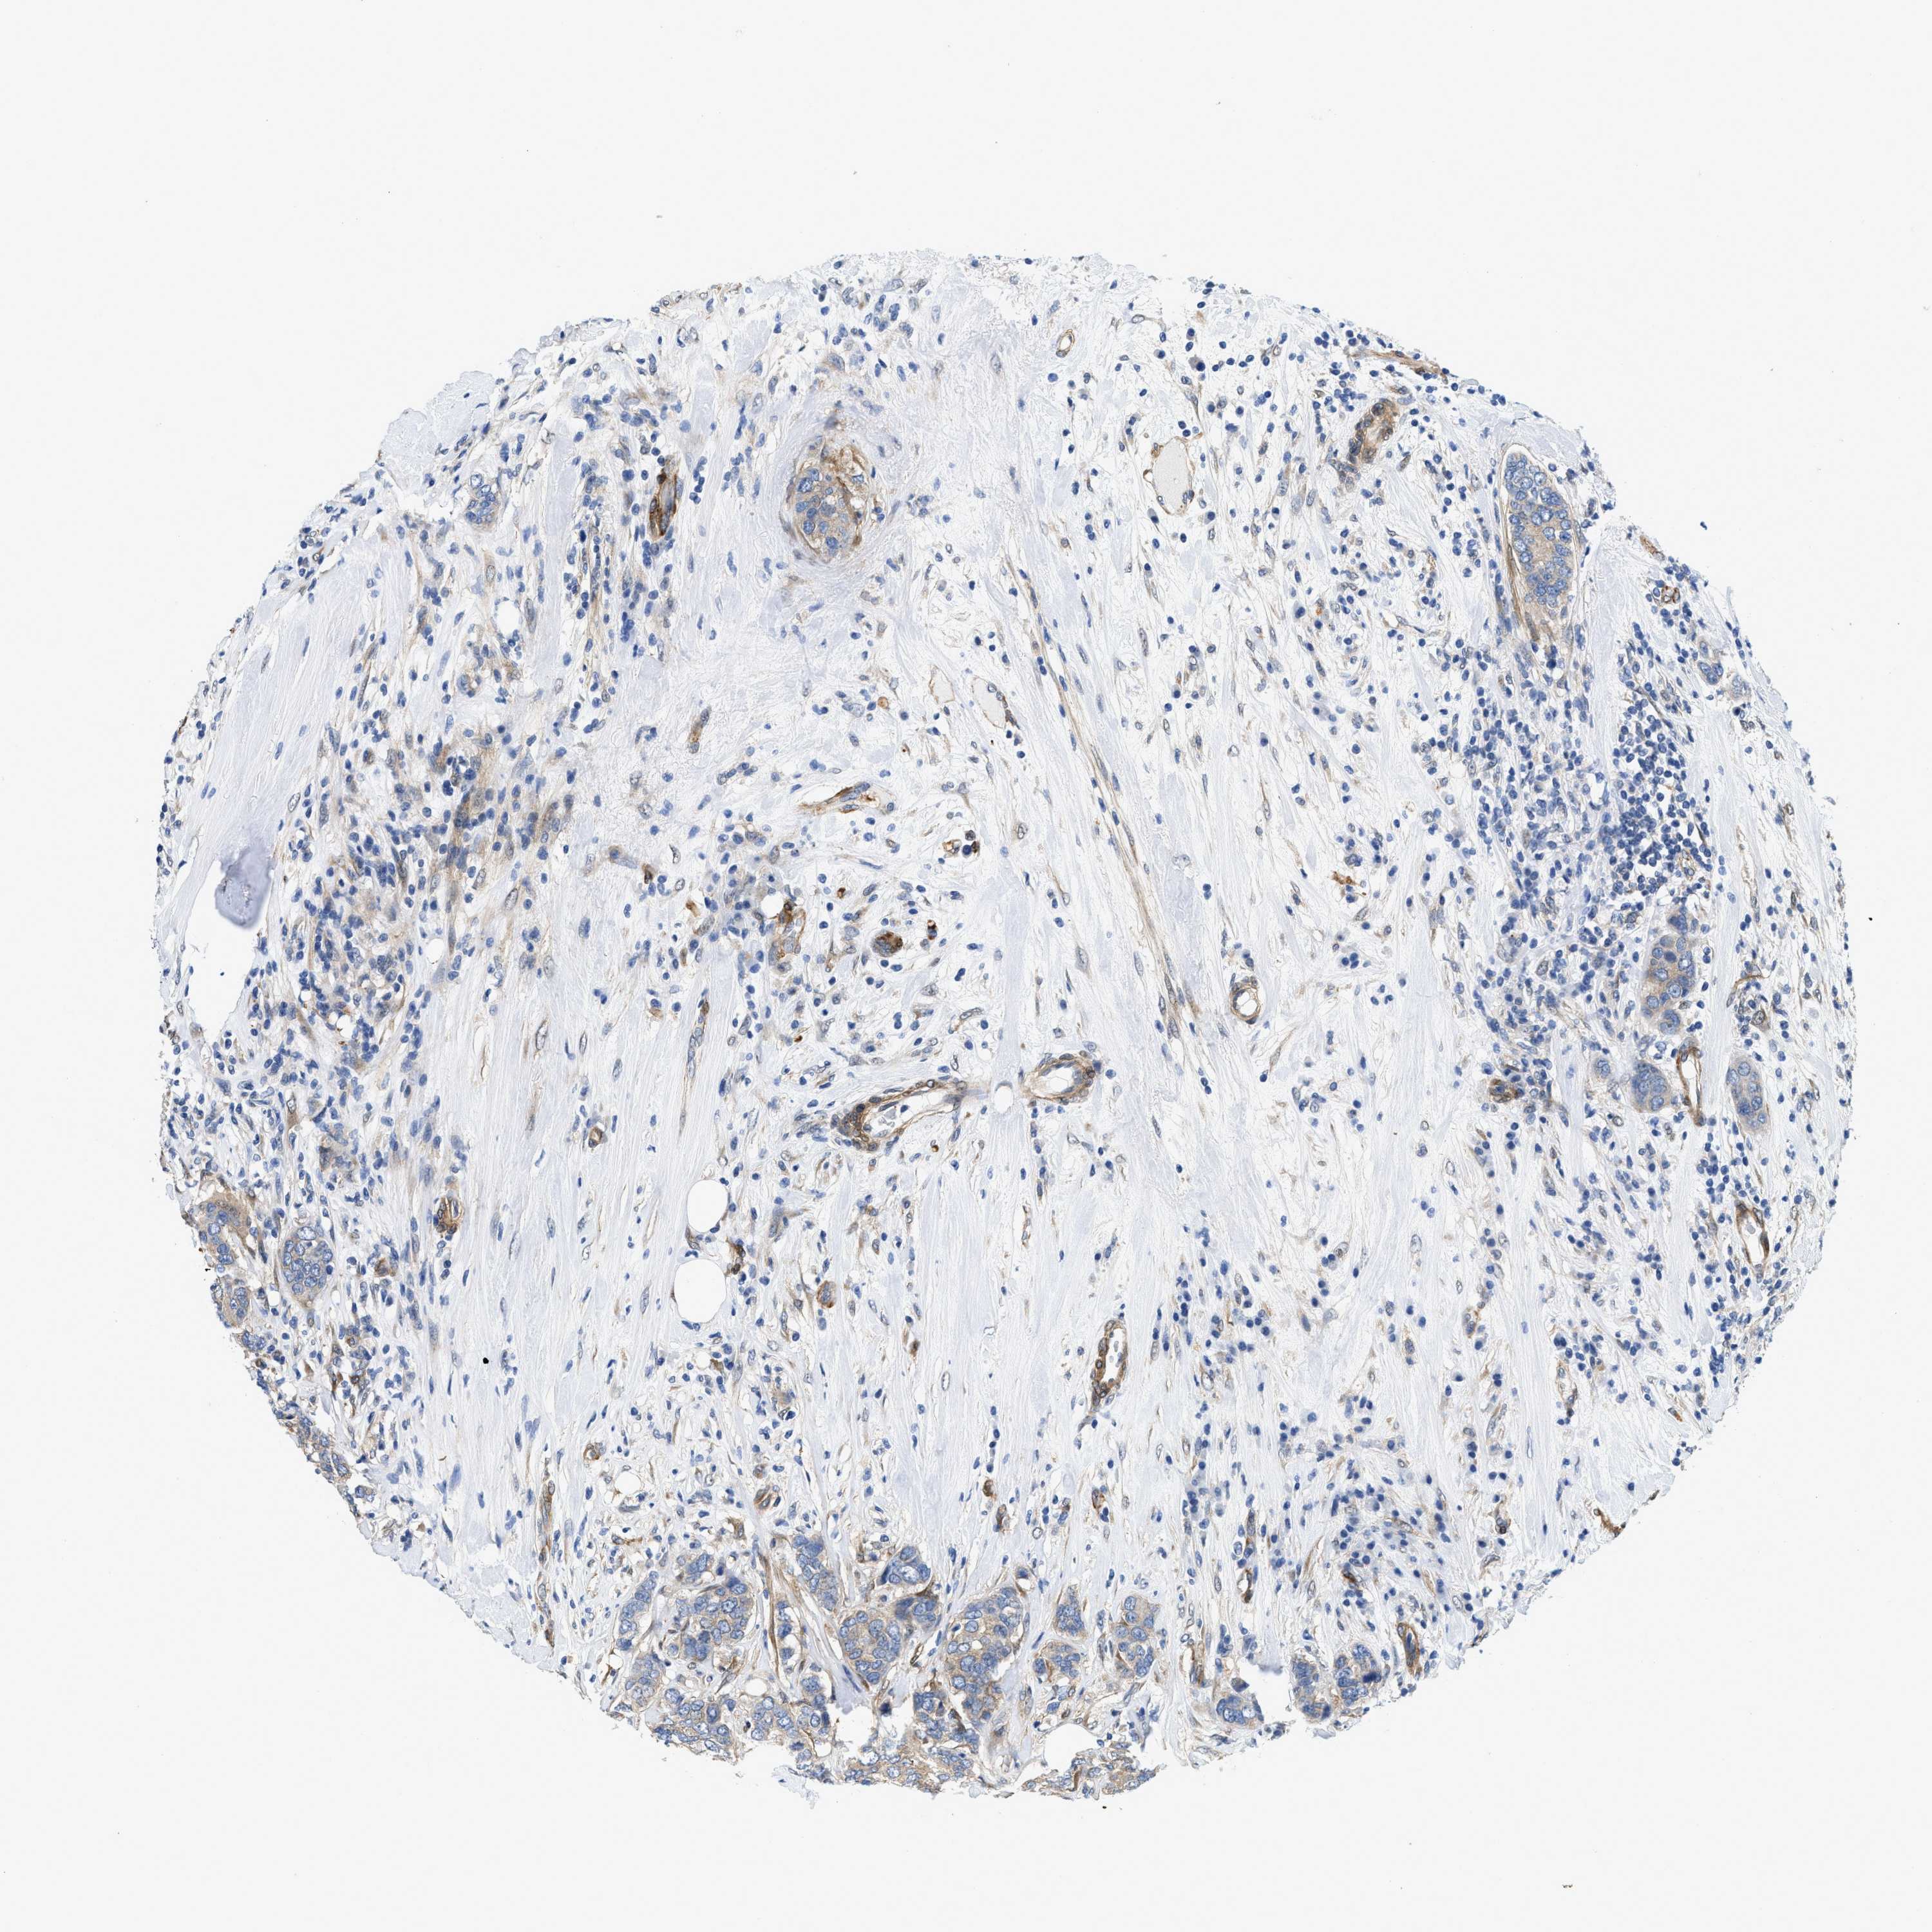

CANCER BREAST CANCER Show tissue menu

BRCA TCGA BRCA VALIDATION PROTEIN EXPRESSION

Breast cancer

Human cancer